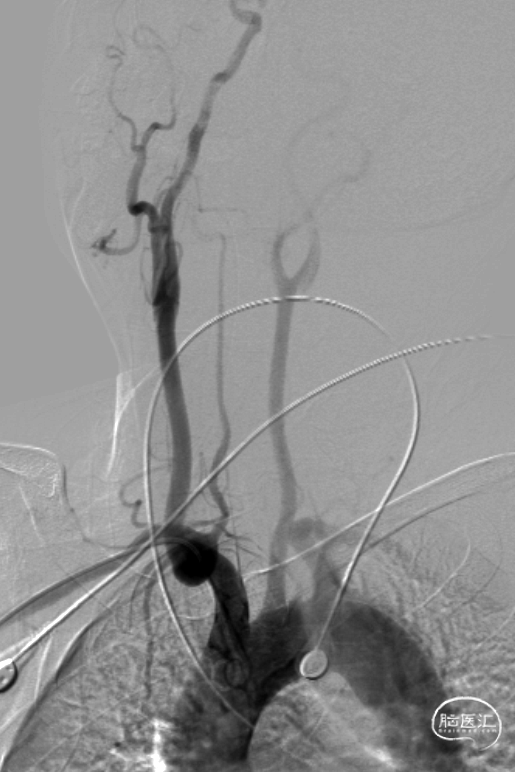

气管插管全麻。6F 指引导管、5F多功能管、泥鳅导丝同轴,将指引管放置于右侧椎动脉V2段。路径图下,将Synchro-14 微导丝引导SL-10微导管导管小心通过椎基底动脉次全闭塞处,放至右侧大脑后动脉P1段。更换为Trensend-300cm微导丝,撤出SL-10微导管。

分别应用2.5mm×15mm、3.25mm×15mm球囊,仔细定位后,以6ATM命名压缓慢扩张。

沿微导丝送入XT-27微导管至基底动脉远端,退出微导丝,送入Neuroform EZ 4.0mm×20mm颅内支架,准确定位后释放于狭窄处。观察支架位置良好,残余狭窄轻。